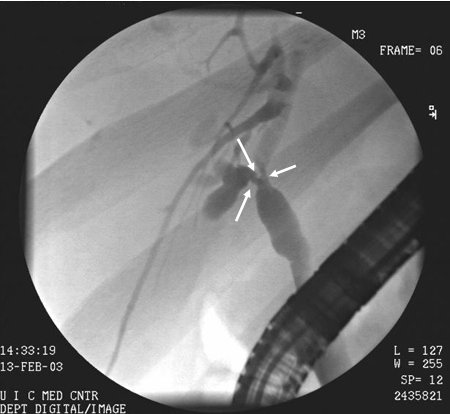

Colangiocarcinoma

CPRE de colangiocarcinoma hilar: tumor de Klatskin com estenose da bifurcação do ducto (setas)

Do acervo de Dr. Joseph Espat; usado com permissão